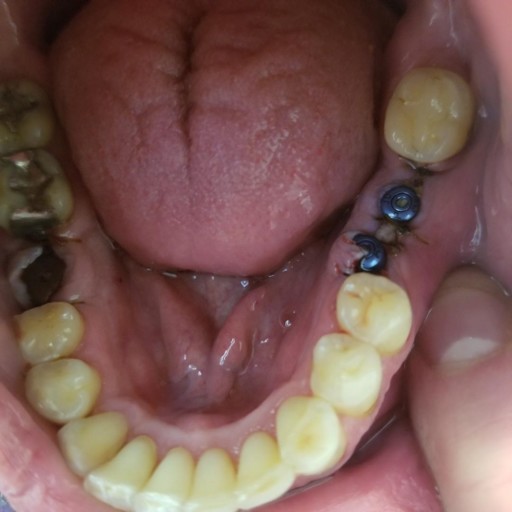

I have very bad Periodontal disease

I have Metlife insurace and Gateway Dental. I was told that the only way I can get Implants, if it is deemed a medically nessesity. I suffer from depression and Hydrocephalus, anxeity and ptsd. would i be a canadite for implants instead of dentures. Im 31 soon to be 32..and haveing to wear dentures will only make me feel bad and i will not want to smile due to the amount of gums that are on dentures compared to implants. My gums are badly infected and my teeth are very lose and i have many chipped teeth. Any advice will be greatly appreciated..thanks

I understand your concerns.  I advise you to have at least 2 consultations.  Prior to recommending dental implants, a dentist me see the condition of your remaining bone.  Dental implants are supported by the remaining bone and cannot be placed without adequate amount to stabilize the implant.  Unfortunately, dental implants are placed surgically and must integrate for 3-6 months prior to being restored.  During this time, you will need to have a healing denture in place.  Once they are healed, the restorative process begins.  There are implant supported dentures as well as hybrid restorations that look and feel natural.  A hybrid restoration has minimal appearance of "tissue" and locks into place on the dental implants.   Many surgeons are prepared to work with patients that have dental fears and anxiety.  The first step is to schedule a consultation, find a doctor you feel comfortable with and understands your fears and expectations.  Next schedule for the extractions, as bad as the teeth are you are describing, you need to ge the infections out of your body as soon as possible.  You will begine to feel so much better without the infection and will be soon on your way to the smile you long for and the confidence it will bring.